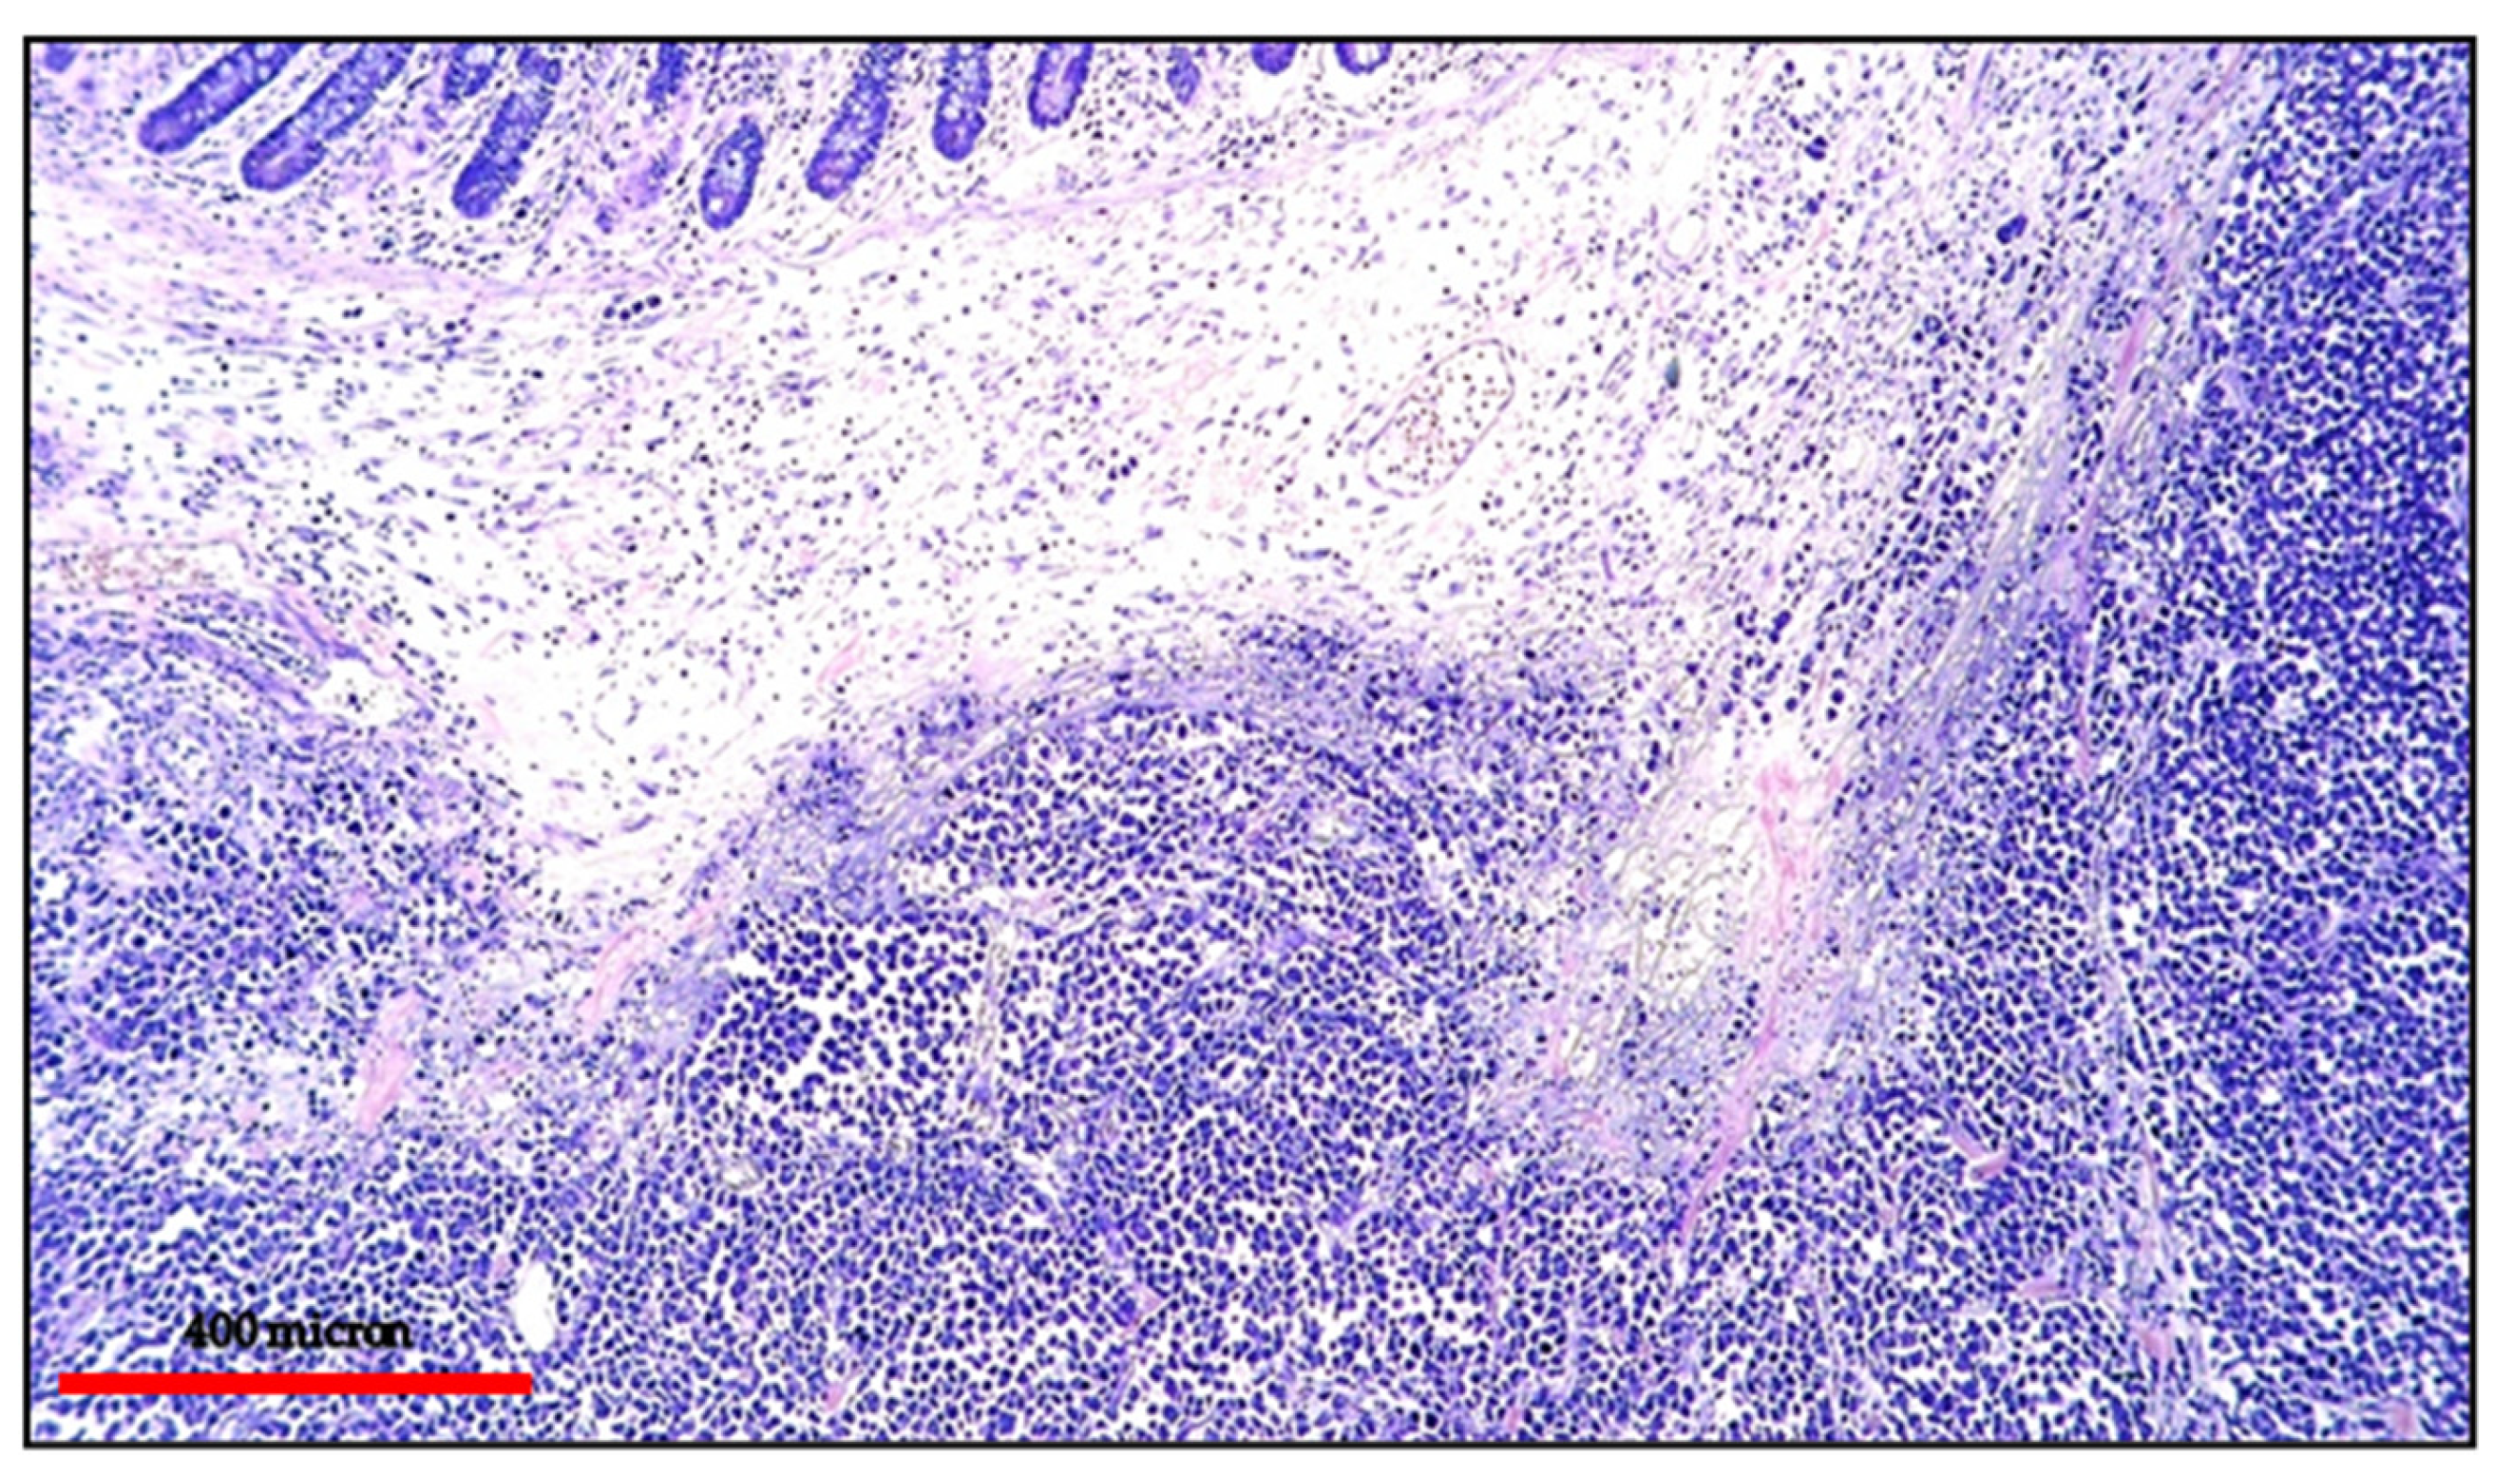

The neoplastic cells are large-sized resembling immunoblasts (IBs) or PBs or displaying an anaplastic morphology (Figure 4 and Figure 5).

Figure 4.

EC-PEL of the ileum: low power view of the neoplastic proliferation involving the bowel wall (Giemsa staining, magnification 100×; original image from Prof Ascani).

Figure 5.

EC-PEL of the ileum: high power highlighting the morphological details of large neoplastic cells with prominent nucleoli (Giemsa staining, magnification 400×; original image from Prof Ascani).